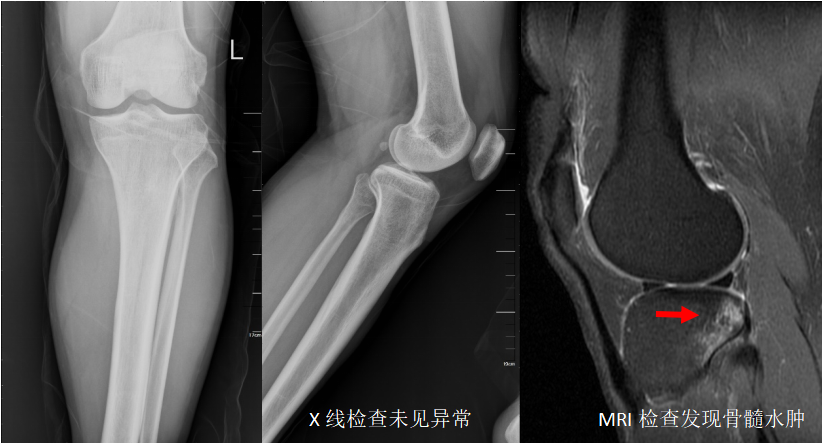

然而X线检查并非十全十美,它对肌肉软组织的分辨率低、仅显示照射范围内所有器官的重叠影像,对重叠部位、复杂部位、细微骨折等容易出现漏诊、误诊的情况。

磁共振检查对隐匿性骨折、外伤伴发的肌肉、肌腱、软骨损伤非常敏感。

磁共振成像(MRI),是利用核磁共振原理,根据人体在外置磁场中发出的电磁波而处理形成图像的一种检查,对软组织分辨率极佳,对肌肉、韧带、神经都能清晰显示。

对于怀疑骨折后伴发有软组织、肌腱、韧带、软骨损伤的患者需要进一步MRI检查。